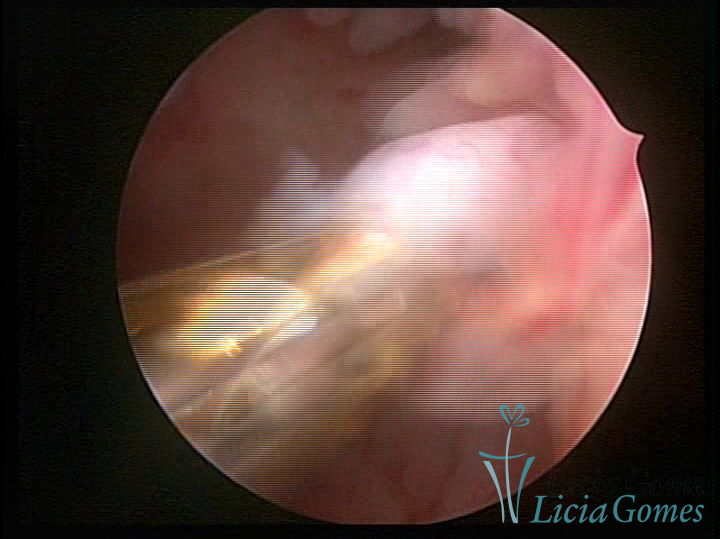

A histeroscopia permite analisar as características da superfície endometrial, não podendo avaliar a profundidade ou o grau de invasão miometrial.

Este pode apresentar uma gama variável de aspectos macroscópicos, com aspecto pseudopolipoide; lembrando tecido cerebroide ou com reação deciduoide;a vascularização superficial é mais evidente e com vasos em formatos de saca-rolha ou espirais visualizando também a vascularização com atípias, com aumento do calibre dos vasos superficiais, pode ser encontrado também tecido em necrose, poderá haver um pequenos dendritos (papilomatoso).